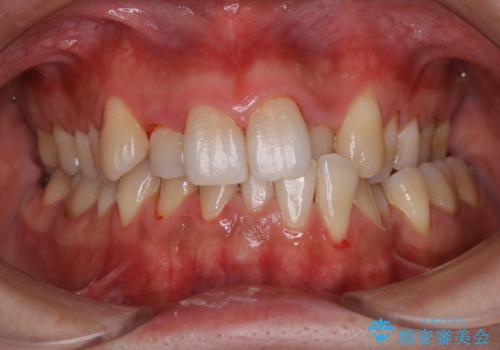

1年ぶりの歯医者でクリーニング

- 忙しく歯科医院でのメンテナンスが1年ぶりとのことで来院されました。PMTC60分コースを行いました。